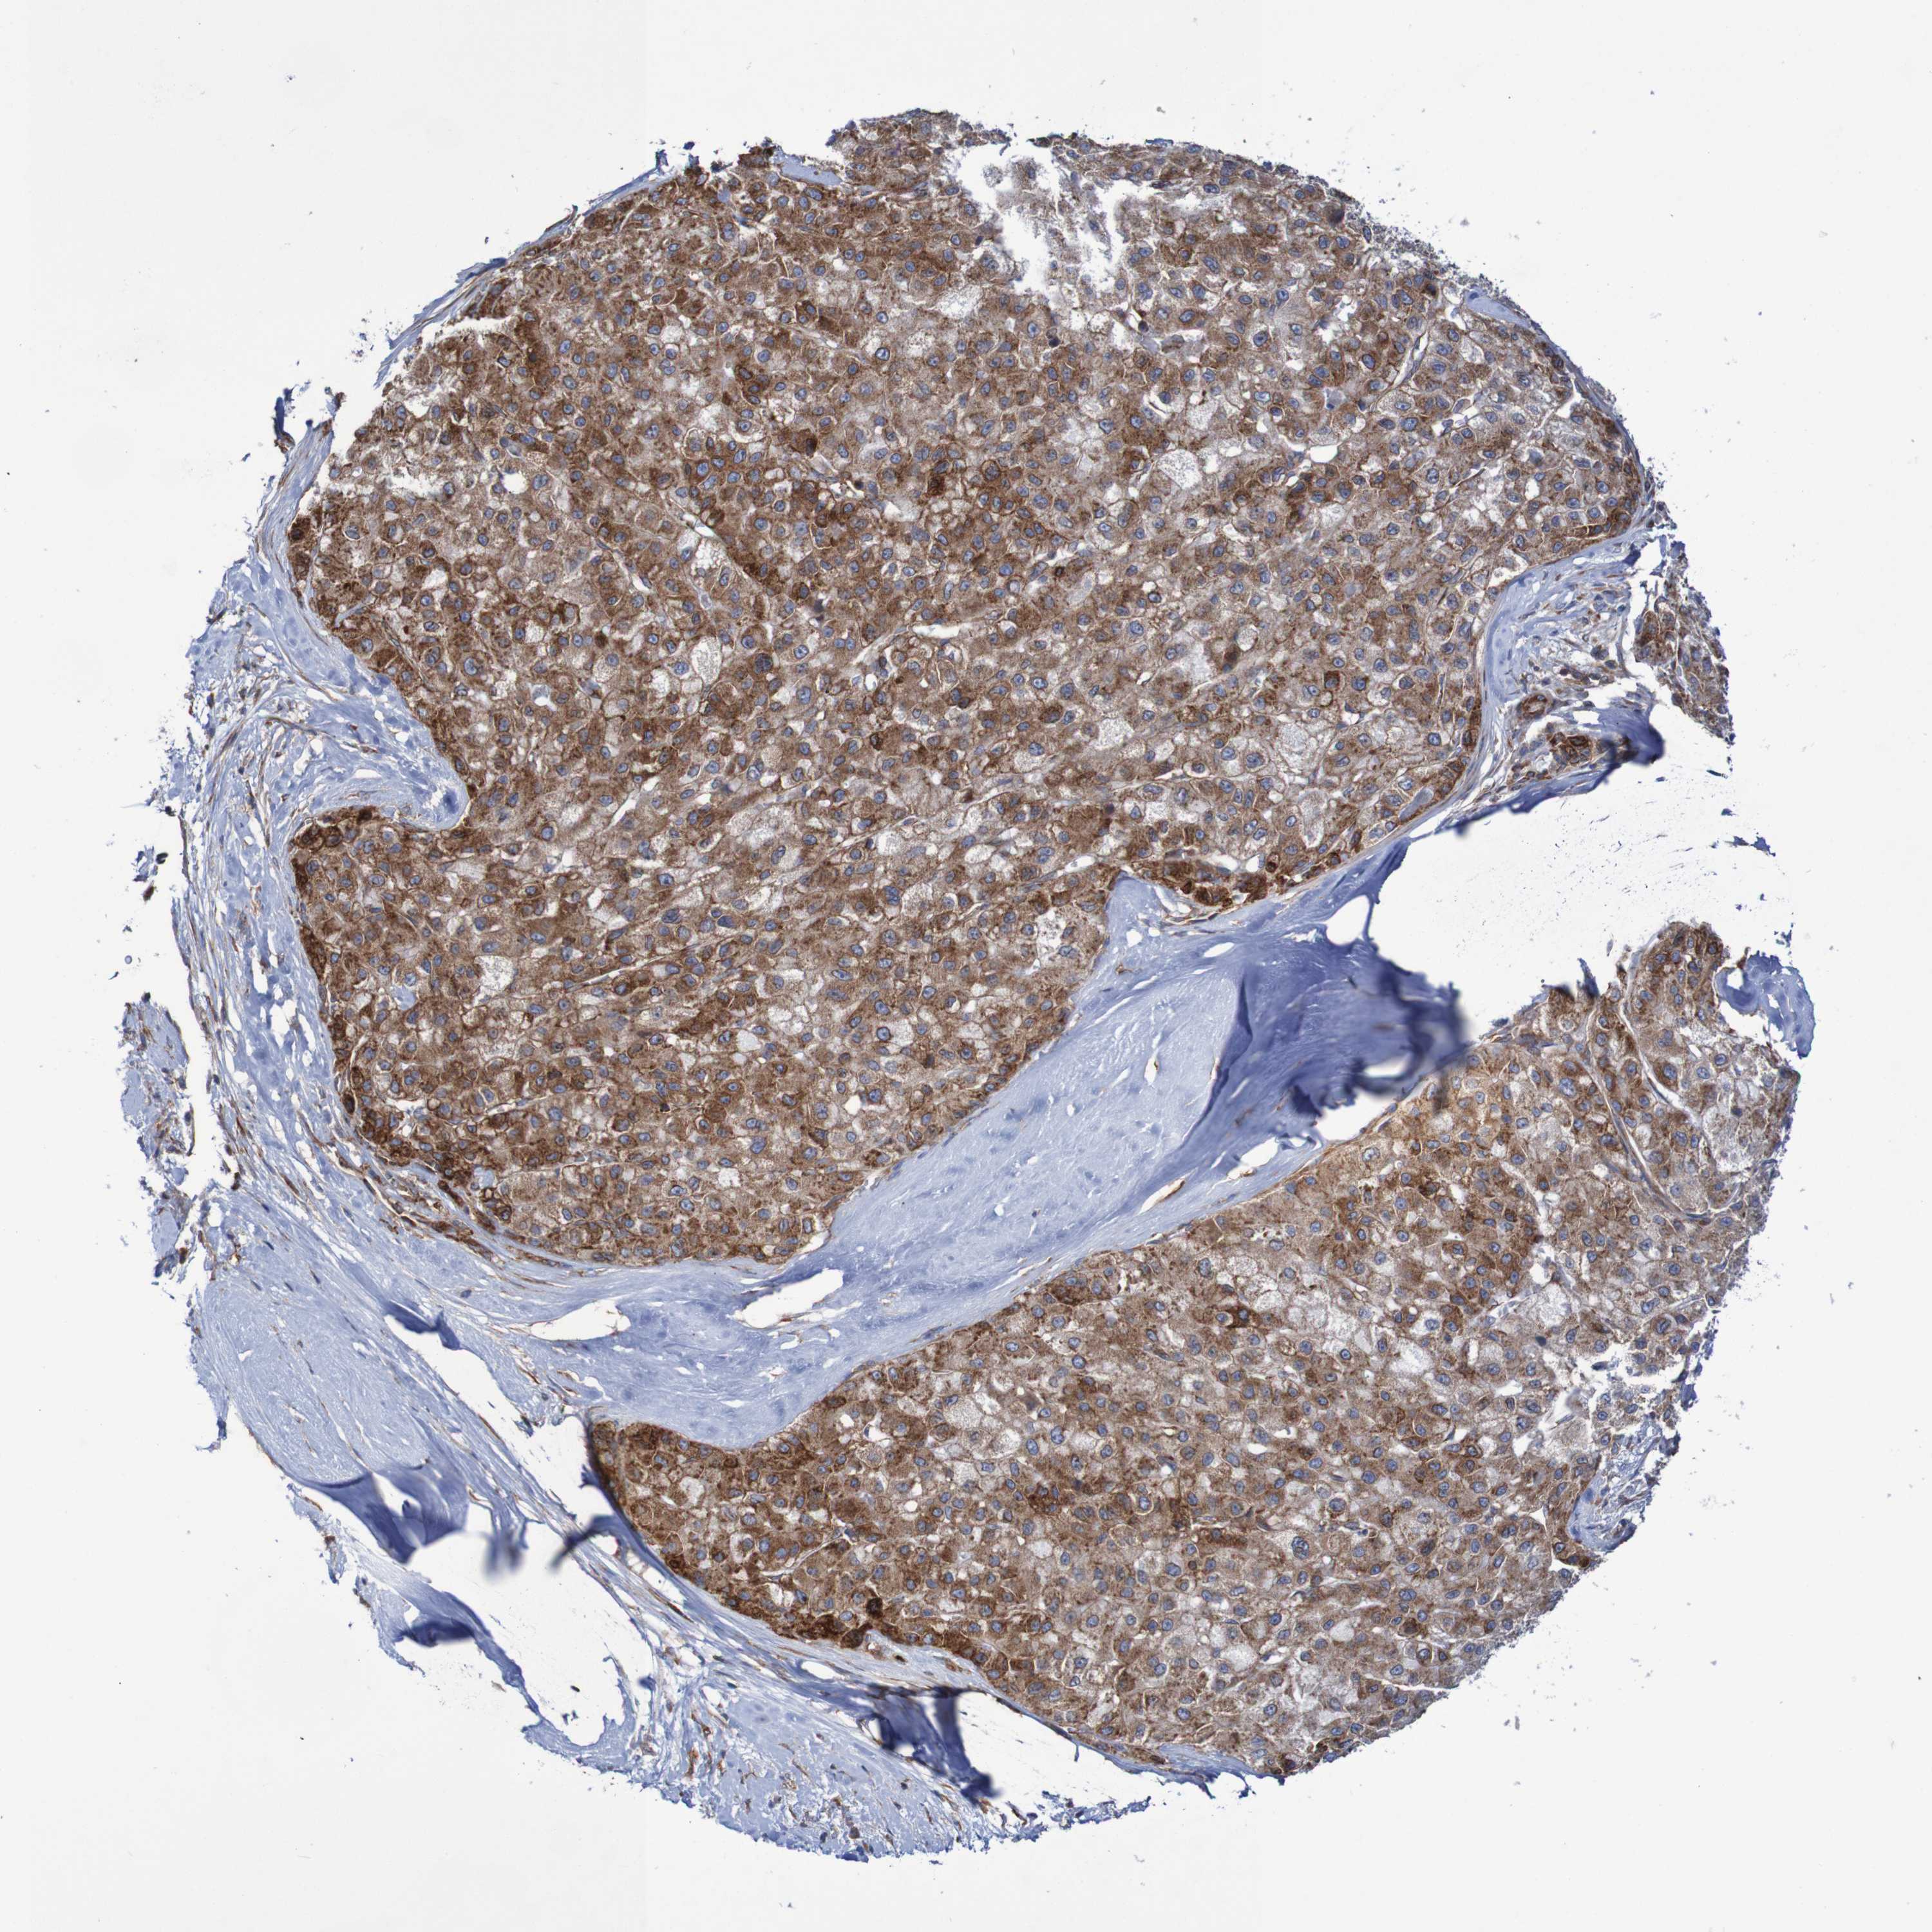

LIVER CANCER - Protein expressioni

A mouse-over function shows sample information and annotation data. Click on an image to view it in a full screen mode. Samples can be filtered based on level of antibody staining by selecting one or several of the following categories: high, medium, low and not detected. The assay and annotation is described here.

Note that samples used for immunohistochemistry by the Human Protein Atlas do not correspond to samples in the TCGA dataset.

Antibody stainingi

Antibody staining in the annotated cell types in the current human tissue is reported as not detected, low, medium, or high, based on conventional immunohistochemistry profiling in selected tissues. This score is based on the combination of the staining intensity and fraction of stained cells.

Each image is clickable and will lead to virtual microscopy that enables deeper exploration of all samples and also displays staining intensity scores, fraction scores and subcellular localization as well as patient and tissue information for each sample.

Antibody HPA022997

Antibody CAB011205

Staining

High

Medium

Low

Not detected

Intensity

Strong

Moderate

Weak

Negative

Quantity

>75%

75%-25%

<25%

None

Location

Nuclear

Cytoplasmic/membranous

Cytoplasmic/membranous,nuclear

Cholangiocarcinoma

Carcinoma, Hepatocellular, NOS